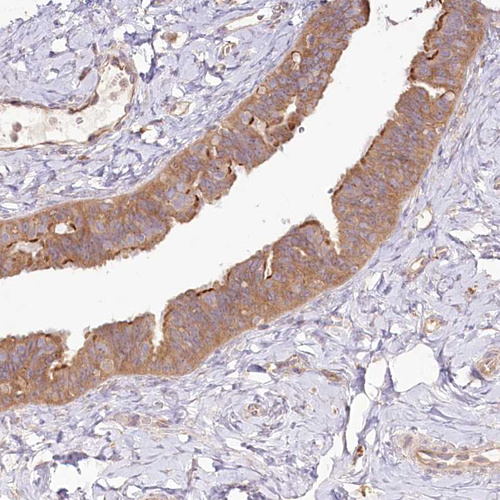

Immunohistochemical staining of human lymph node shows moderate cytoplasmic positivity in germinal center cells.